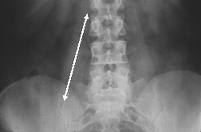

腰椎---病例探討-----髂腰肌筋膜炎

『髂腰肌』更進一步從解剖結構細分為由腰大肌及髂肌所組成,由於起始點不同,但因終點都在股骨頭的近端的小轉子同一肌腱上,一般統稱為髂腰肌,現分別介紹如下:1.腰大肌psoas major:(psoas=腰部肌肉)腰大肌的肌肉起點在第十二胸椎第一腰椎至第五腰椎橫突的位置,結束於股頭的上端。2. 髂肌ilicas muscle:起源至髂骨窩內側,止點同腰肌同一位置。

『髂腰肌』就是你的身體的『西螺大橋』,連接你身體的上半身與下半身;而同時這條肌肉解剖的走向又是從後面胸椎第十二節、腰椎第一、二、三、四、五橫突,往前往下走到大腿骨關節。所以,『髂腰肌』又是連接身體前、後最重要的一條肌肉。『髂腰肌』會左右你的脊椎及骨盆及大腿的彎曲度。當『髂腰肌』縮短太緊時,會帶動骨盆向前傾,增加脊椎前凸的幅度,此會將上半身重量完全集中置於腰椎上,那會造成腰椎椎間盤凸出或是關節過度磨損及長骨刺、脊椎滑脫等多項問題。常見門診有些朋友練瑜珈後彎,因為,『髂腰肌』縮短太緊,實在是沒有辦法做的很好,又想好好保護脊椎的活動度,此時,就應該先多多伸展『髂腰肌』。